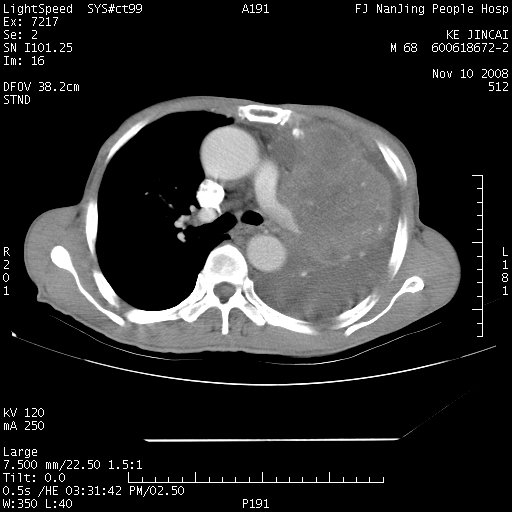

是个很有看头的病例,咋人气那么不旺?没多少人兴趣呢?这个病例几大怪:1   恶性肿瘤侵犯心肌左房怪,心肌一般不会被恶性肿瘤侵犯吧?2   左下肺均匀实变怪,内无含气,有别一般不张实变,含气肺泡完全为液体取代,而非一般不张实变的肺萎陷,冷不丁还以为是肿大的脾脏3   肿瘤本身怪,像tb肺不张4   这么有看头的病例没人气怪。呵呵。

左肺恶性肿瘤侵犯肺动脉,左心房内瘤栓,胸膜转移。

左肺恶性肿瘤侵犯肺动脉,左心房内瘤栓,胸膜转移,少见,学习了。